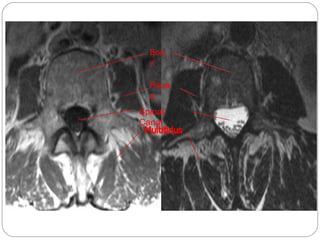

Magnetic Resonance Imaging

(MRI)

What is a MRI?

• The use of a High Power Magnet (.3

-2.0Teslas)To align hydrogen atoms in

the body to which a radio wave

frequency is applied to produce an

image

HigherTesla level= increased resolution

1. Also called “MRI”

2. Image formed by transmitting and receiving radio

waves inside a high magnetic field

3. Image “slices” reconstructed by computation

4. The image formed is related to:

1. Scanner settings

2. Patient hydrogen density

3. Patient hydrogen chemical/physical

environment

5. Image display on computer or multiple films

Indications for MRI

Diagnosing multiple sclerosis (MS)

Diagnosing tumors of the pituitary gland and brain

Diagnosing infections in the brain, spine or joints

Visualizing torn ligaments in the wrist, knee and

ankle

Visualizing shoulder injuries

Diagnosing tendonitis

Evaluating masses in the soft tissues of the body

Evaluating bone tumors, cysts and bulging or

herniated discs in the spine

Diagnosing strokes in their earliest stages